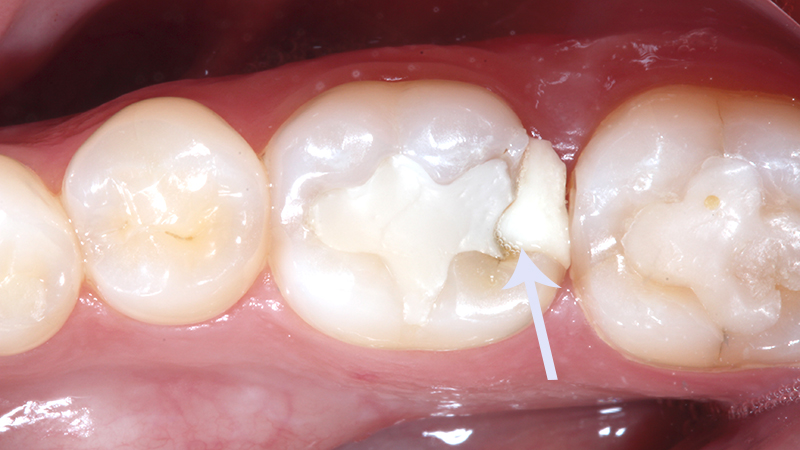

Restaurações dentárias antigas e danificadas

Restaurações antigas que começam a se deteriorar podem permitir a infiltração de bactérias no dente, atingindo a polpa. Muitas vezes, esses problemas passam despercebidos até que a infecção se torne significativa e cause dor.

Infiltração no dente

A infiltração de materiais usados em tratamentos dentários anteriores pode abrir caminho para bactérias que atingem a polpa, causando inflamação e infecção. Esse problema costuma ser comum em restaurações mal adaptadas ou desgastadas.